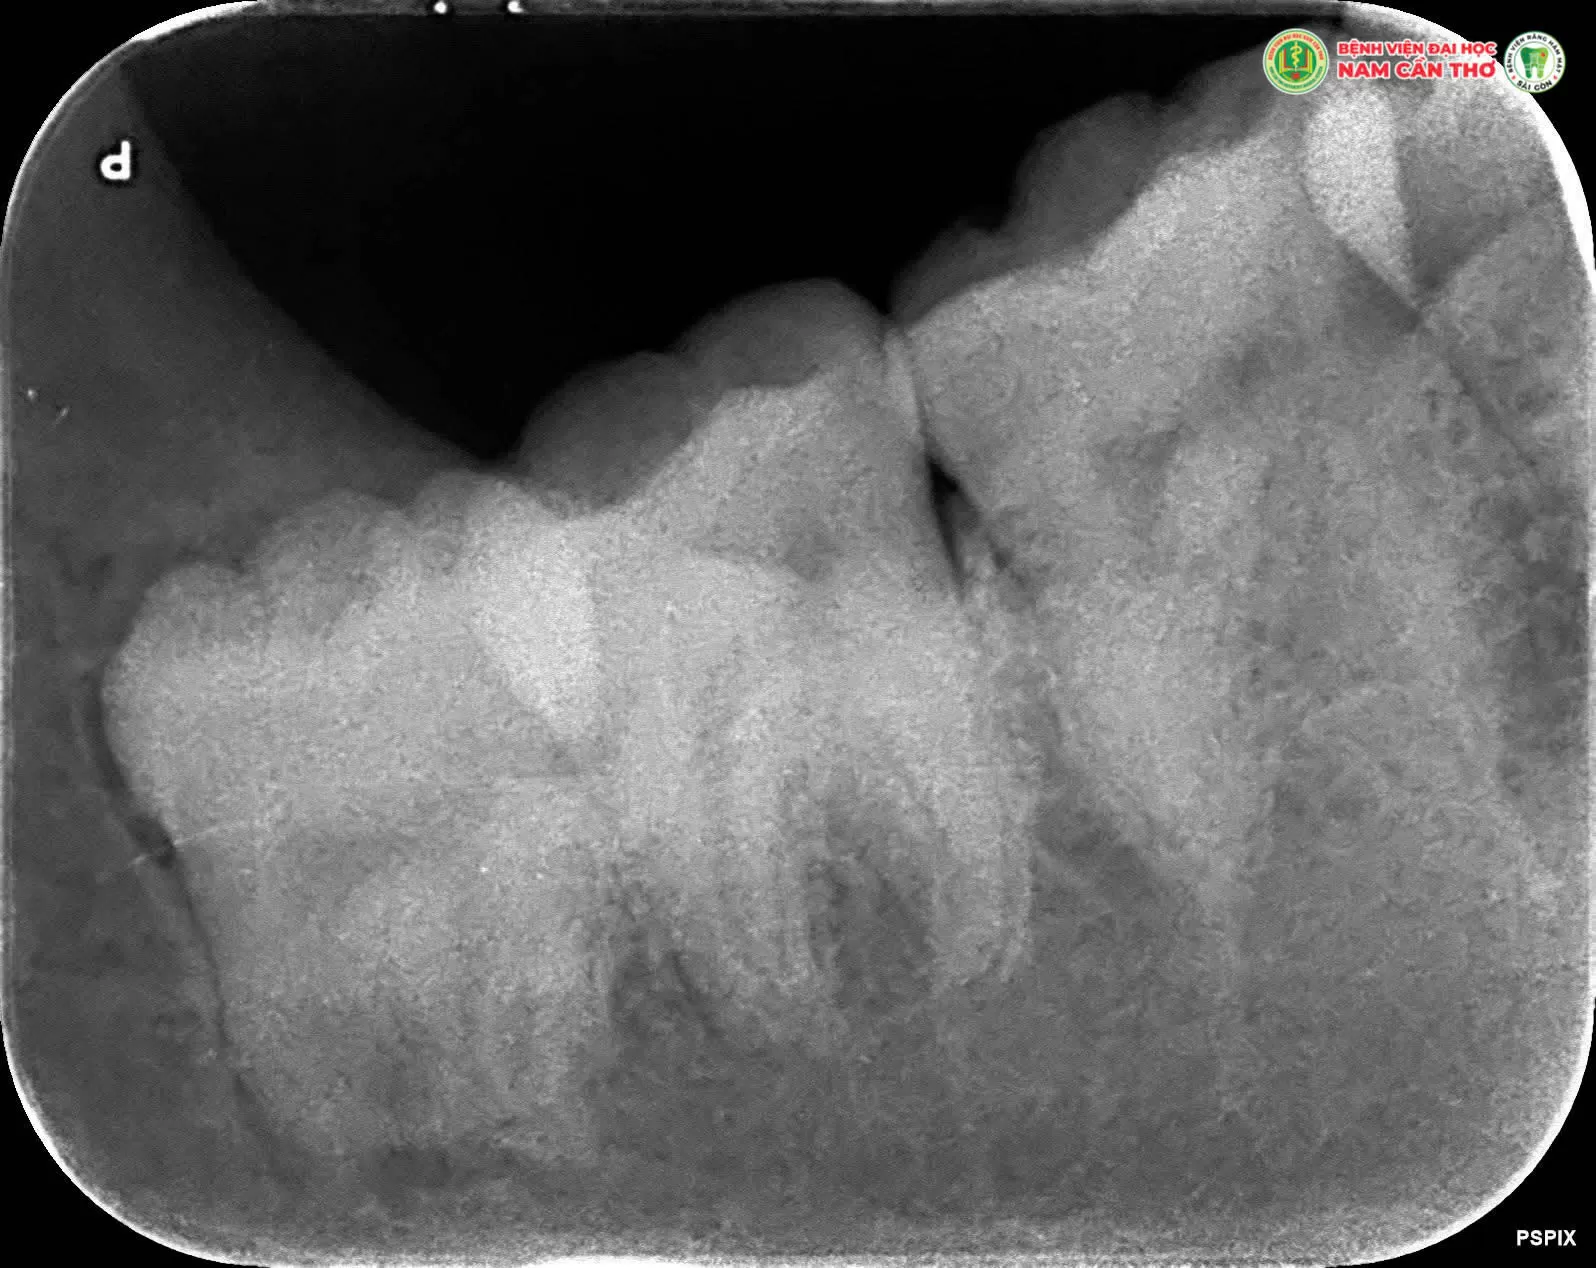

✨Răng khôn thường mọc lệch, mọc ngầm hoặc chen chúc gây đau nhức viêm nhiễm và ảnh hưởng đến các răng bên cạnh. Việc nhổ răng khôn đúng thời điểm đúng kỹ thuật là cần thiết để đảm bảo sức khỏe răng miệng lâu dài.